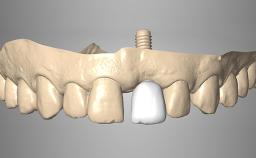

Rehabilitating an Edentulous Maxilla with a Fixed Dental Prosthesis Using a DSD-Guided Approach

A 60-year-old man was referred to the Center of Excellence for Prosthodontics and Implant Dentistry (CEPI) of the School of Dentistry of the University of São Paulo, Brazil for implant therapy. Anamnesis, clinical examination, and radiographs revealed esthetic and functional problems, the absence or structural compromise of various teeth (16–11, 21, 22, 24, 25, 37, 45, and 48), periodontal and endodontic problems (17 and 27), implant fracture (46), and occlusal disorders . The patient reported that he was undergoing treatment for cardiovascular diseases.